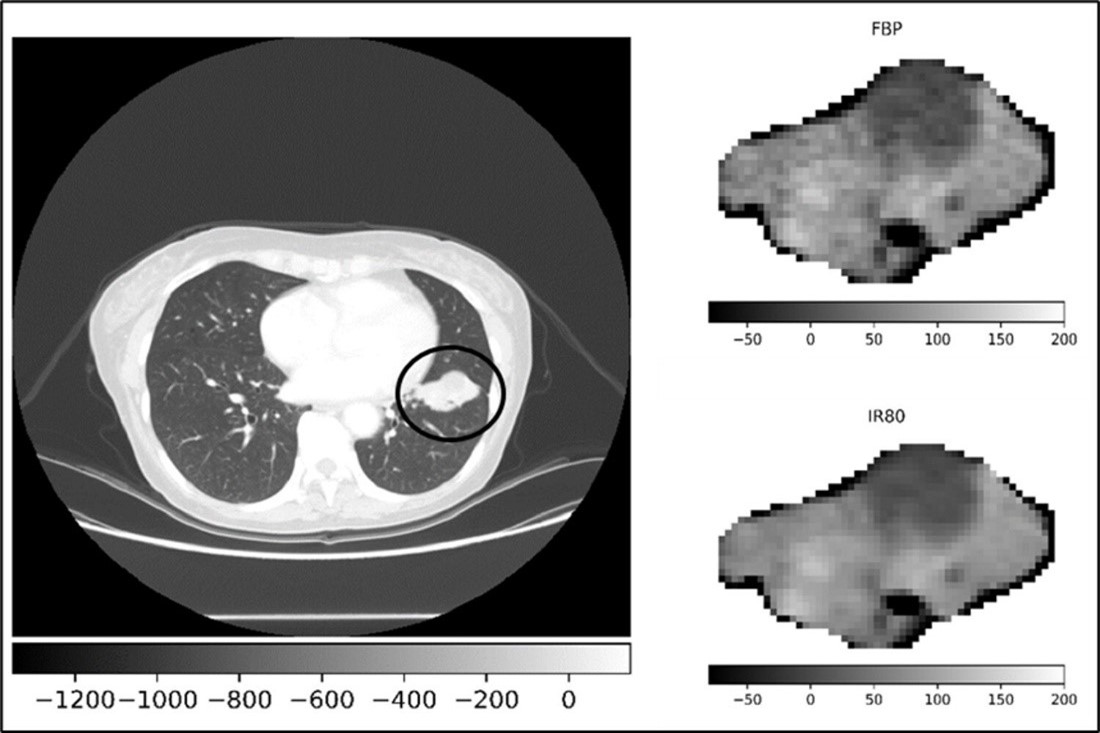

Lung cancer is the leading cause of cancer death among both men and women. To date, radiomics has been used to aid in lung cancer diagnosis, histologic classification and mutation detection, as well as to predict oncologic outcomes. At the IEO, lung cancer has been the focus of several efforts by the radiomics team. The role of radiomics and artificial intelligence in the early detection of lung cancer using low-dose CT (computed tomography) has been studied, with the goal of developing predictive models for the detection of malignant nodules and early prediction of response to therapy. Other projects have evaluated the possibility of predicting lung cancer mutation status and overall survival based on radiomic analysis of CT images. The radiomic team was also involved in investigating the more methodological aspects of these studies. In particular, the various classification methods and reproducibility of radiomic features in CT images were studied. The IEO is actively involved in the international multicenter BLUESKY study, which aims to evaluate the prognostic role of radiomics in predicting the efficacy of chemo-immunotherapy for locally advanced and inoperable non-small cell lung cancer. Alongside h CT, the possibility of predicting overall survival and disease-free survival by radiomic analysis of 18F-FDG PET images is being investigated. The analysis relies on methodological evaluations, including the evolution of the robustness of radiomic features according to image acquisition parameters changes and comparing different tumor lesion segmentation techniques.